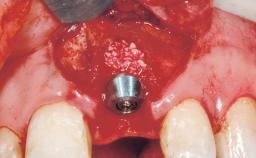

A 42-year-old female patient was referred to our clinic at the School of Dentistry of the University of São Paulo in November 2004, presenting a deficient restoration in the upper left central incisor. The clinical examination revealed no gingival retraction or any signs of gingival inflammation and, therefore, previous periodontal treatment was not considered. The patient presented a high lip line at full smile and a thin tissue biotype. This combination characterized a high-risk situation from an anatomic point of view, which required careful preoperative planning and cautious surgical execution.

Placement Protocol Immediate implant placement

Tooth Site Maxillary incisor or canine

Socket Morphology Single-root socket

Socket Integrity Sufficient, with intact bone walls

Bone Volume Sufficient, with intact walls

Type of Implants One-Piece